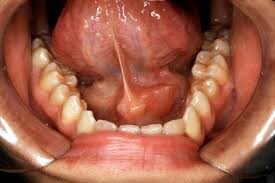

Early treatment of a swollen salivary gland — particularly when caused by a stone — could save you from developing an infection. The National Health Service recommends increasing your saliva production by drinking plenty of water and chewing sugar-free gum. The Government of Alberta suggests gently massaging the stone to help dislodge it.

If you are unable to treat it at home, your doctor or dentist may be able to push the stone out by pressing the submandibular gland or pull it out by using a small instrument, according to Merck Manuals. In rare cases, the stone may need to be removed surgically. If you suffer from a condition that causes salivary gland stones, receiving treatment to alleviate other symptoms may also reduce your risk of developing stones.

If you have an infection in your submandibular gland, your doctor can prescribe antibiotics and, if necessary, drain any pus from an abscess. Swelling caused by a tumor can be addressed by removing the tumor through a surgical procedure. Cancerous tumors should be treated urgently and will likely require monitoring.